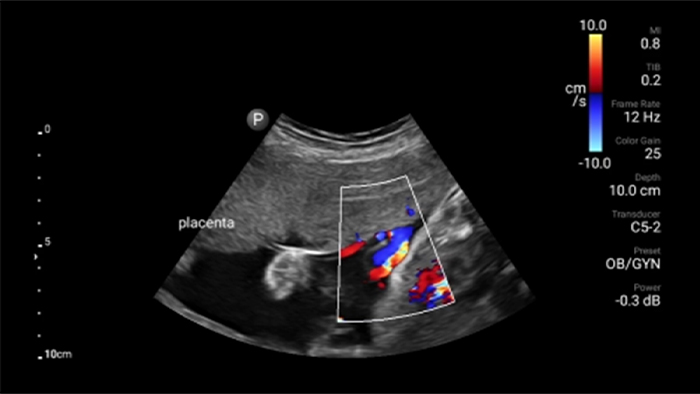

• Rango extendido de frecuencias de operación de 4 a 1 MHz • 2D, Doppler a color, Modalidad M, XRES avanzado e imágenes armónicas multivariables • Imagenología de alta resolución para aplicaciones abdominales y cardíacas: optimizaciones de preajustes de imágenes cardíacas, gineco-obstétricas, pulmonares, abdominales y FAST.